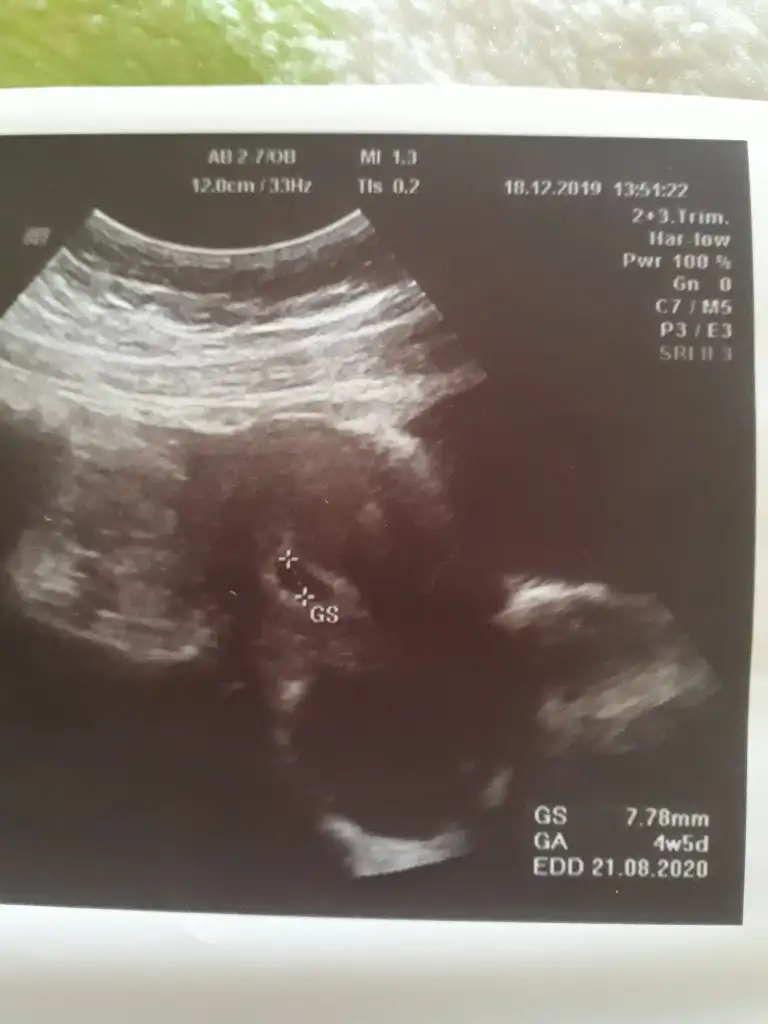

Kızlar gittik hastaneye kese görüldü 4 haftalık dedi sat a göre 6 hafta 5 günlük demkki geç dönlenme olmuş 10 gün sonra tekrar gidicem kalp atışı bebek icin

Merhaba bayanlar biraz geç kalmışım ama bende 2020 Ağustos annesi olacağım inş 2018 Ağustos annesi olacaktım ama rabbim inş 2sene sonra aynı ayda nasip edecek bana